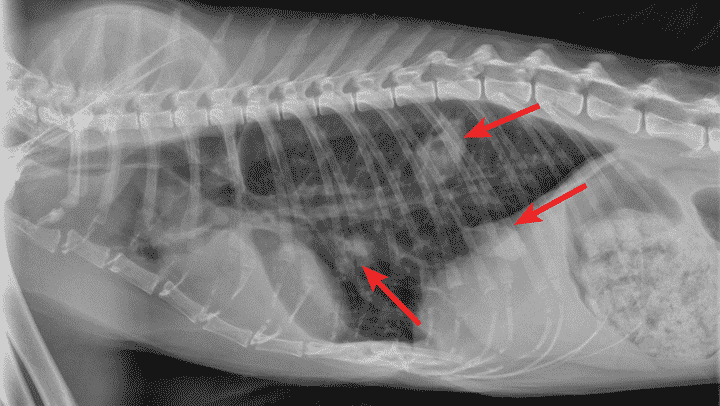

Theo dõi sát sao là chìa khóa: khám lại thường xuyên, chụp X-quang mỗi 2 tuần để kiểm tra tiến triển. Giữ môi trường sạch sẽ, ấm áp, và kiên nhẫn vì hồi phục có thể mất vài tuần. Với sự chăm sóc đúng cách, mèo yêu của bạn sẽ khỏe mạnh trở lại thôi!

Đừng quên khám sức khỏe định kỳ, chụp X-quang phổi nếu cần, phát hiện sớm là cứu cánh. Nếu nhà có mèo bệnh, cách ly ngay và khử khuẩn tay sau khi chăm sóc.